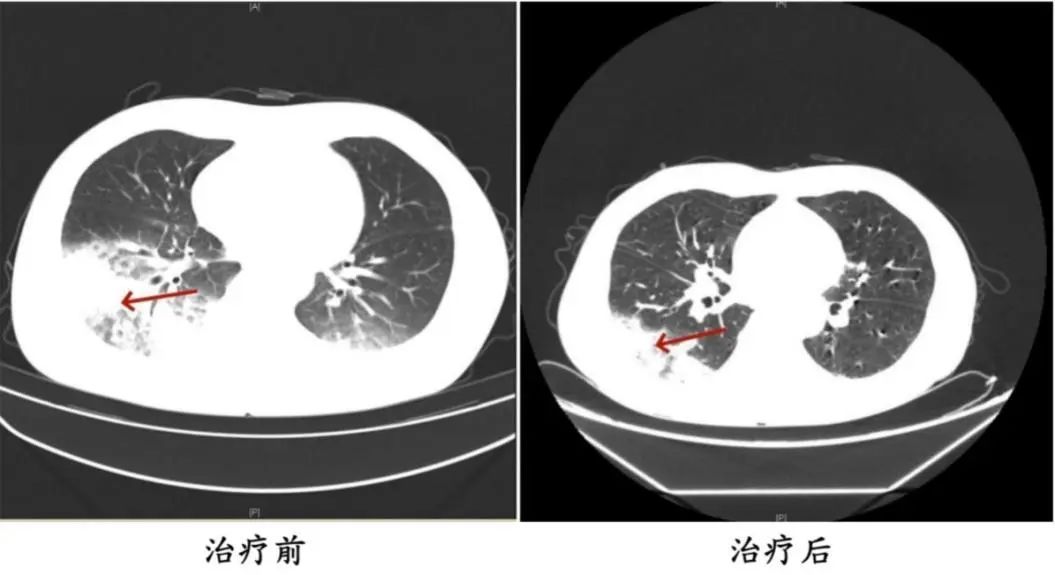

李先生的经历并不少见。2024年,湖南长沙55岁的市民陈先生有许多过去的历史,如2型糖尿病、2型糖尿病性肾病、慢性肾功能不全等。,因持续发热、寒颤和干咳而去医院。检查发现肺部感染严重,抗生素抗感染治疗后效果不佳,患者持续发热,出现意识淡漠的异常表现。

医生询问后发现,陈先生之前开车出差。由于天气炎热,他开始了一台很久没有清洗的汽车空调。他每天在车里呆十几个小时,回来后就出现了上述症状。经检查,最终确诊为军团菌肺炎。

△治疗前后陈先生肺部CT影像